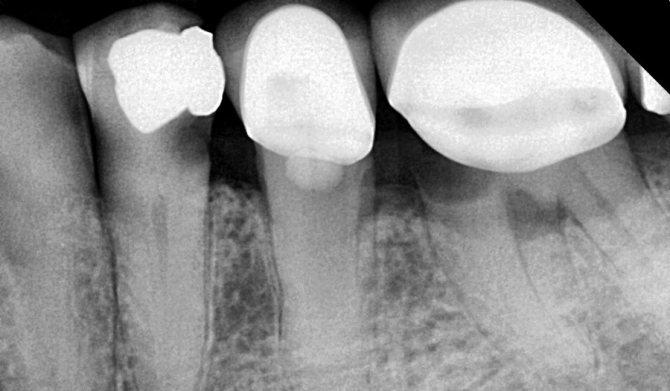

Если стоматолог увидит, что пломба изменила цвет, но не сможет сразу определить кариес, он назначит рентгенологический снимок. Рентген также понадобится в случае, если вторичный кариес возник в депульпированном зубе.

С помощью рентгена можно оценить глубину и локализацию кариозного разрушения. На снимке пломба будет выглядеть как белое пятно, а кариес – как темное.

Лечение обеих форм периодонтита схожее. Его проводят после рентгенографии.

После этого пациент делает рентгеновский снимок, каналы пломбируются специальной гуттаперчей, а затем уже ставится постоянная пломба.

После этого при отсутствии признаков воспаления каналы пломбируют и делают контрольный рентгеновский снимок. Только после этого при следующем визите к врачу проводится постоянное пломбирование. Если эндодонтическое лечение не дает желаемого результата, проводят хирургическое вмешательство — резекцию верхушки корня. Она предусматривает удаление определенной части зубного корня, а также патологического очага в канале.